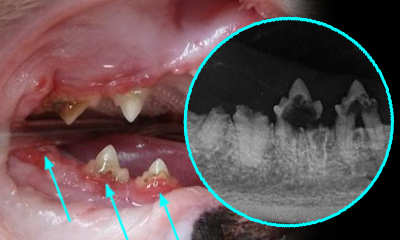

육안으로는 크게 문제가 없는것처럼 보이지만 실제로는 문제가 심각한 증례 사진 서베이 from google image